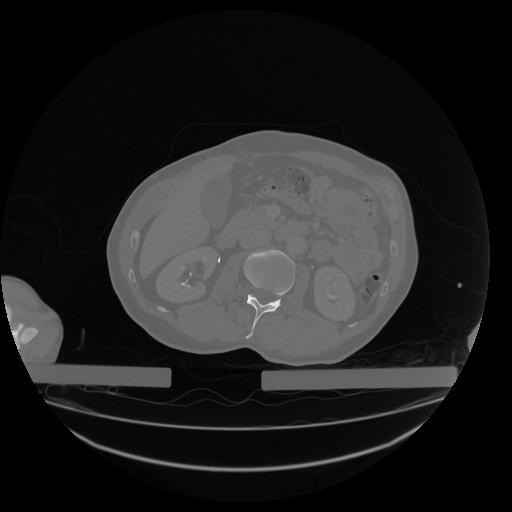

34 CUERPO,CE,Vol,1.0,CUERPO,,